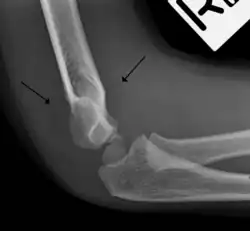

The fat pad sign, also known as the sail sign, is a potential finding on elbow radiography which suggests a fracture of one or more bones at the elbow. It may indicate an occult fracture that is not directly visible. Its name derives from the fact that it has the shape of a spinnaker (sail).[1] It is caused by displacement of the fat pad around the elbow joint. Both anterior and posterior fat pad signs exist, and both can be found on the same X-ray.

The fat pad sign is invaluable in assessing for the presence of an intra-articular fracture of the elbow. An anterior fat pad is often normal. However a posterior fat pad seen on a lateral x-ray of the elbow is always abnormal. The patient will be unable to flex their elbow and requires orthopaedic input.[2]

The posterior fat pad is normally pressed in the olecranon fossa by the triceps tendon, and hence invisible on lateral radiograph of the elbow.[3] When there is a fracture of the distal humerus, or other pathology involving the elbow joint, inflammation develops around the synovial membrane forcing the fat pad out of its normal physiologic resting place. This is visible as the "posterior fat pad sign" and is often the only visible marker of a fracture, particularly in the pediatrics population.